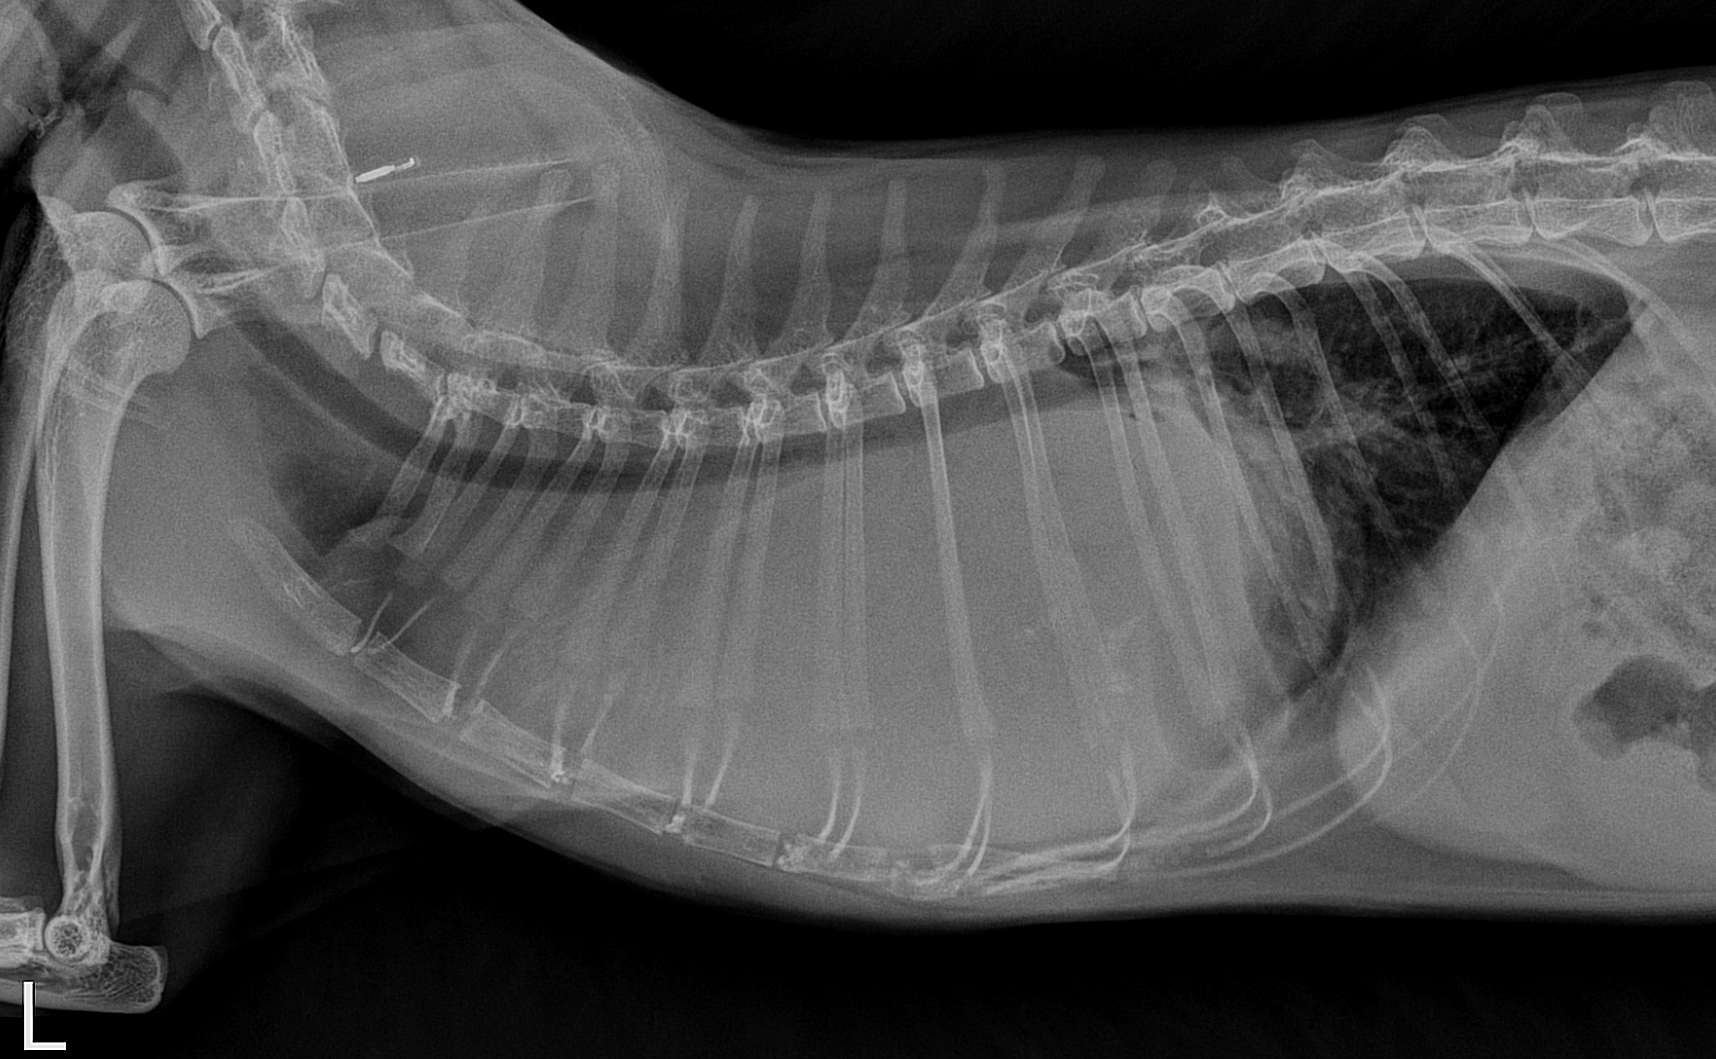

A 7yo MN DSH presents for 10 days of intermittent tachypnea progressing to mild dyspnea. Radiographs were performed. What are your radiographic findings? (that means describe what you see… it does not mean shout out a one word diagnosis!)

There is a large soft tissue mass occupying the cranial thorax, displacing the heart caudally and dorsally. The trachea is also displaced dorsally. The cranial lung lobes are still visible cranial to the mass and are slightly increased in density. The diaphragm is intact and the portion of the abdomen included appears normal.

The findings are most compatible with a cranial mediastinal mass, and thymoma would be considered as the most likely differential diagnosis. Thymic lymphosarcoma could have a very similar radiographic appearance, and usually a biopsy is required to definitively diagnose the tumor type, as aspirates are often inconclusive. No biopsy was pursued in this patient, but ultrasound showed a mass with characteristics typical of thymoma.

The annotated image below indicates the direction of force exerted by the mass on the other mediastinal organs, which can be helpful in trying to identify the origin of the tumor in a case like this.